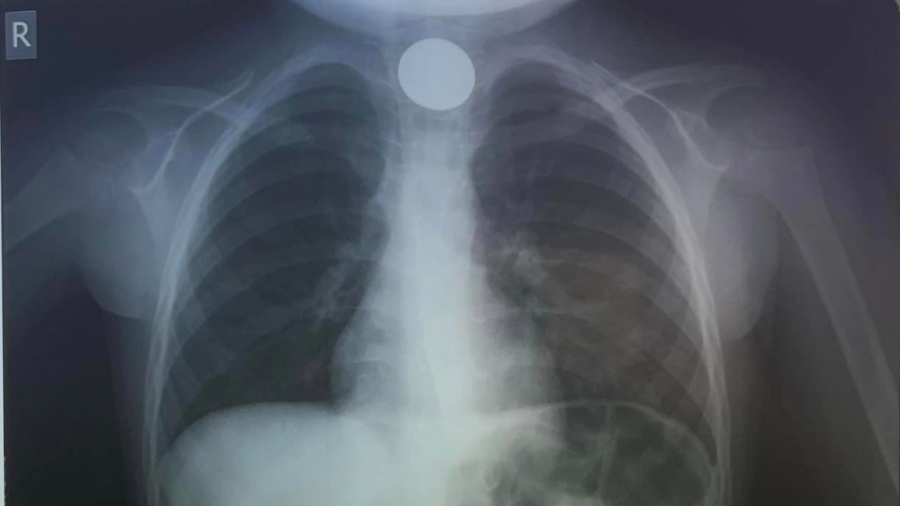

Φυσικά οι θεράποντες ιατροί έσπευσαν να του κάνουν ακτινογραφία, προκειμένου να εντοπίσουν το σημείο που είχε σταθεί το νόμισμα.